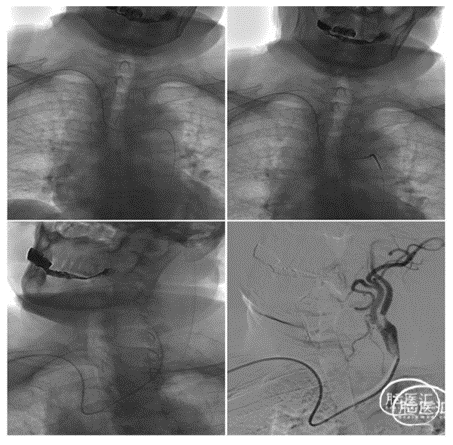

经绕动脉完成的颈内动脉介入通路:

选择4F125猪尾或5F125西蒙或125单弯西蒙形状带6F导引导管较好,没有125导管的情况下,6F导引导管不接Y阀内衬100cm造影导管到位后撤出造影导管,再连接Y阀。可以完成通路建立。

缺点6F导引导管仅能通过7-8mm以下自膨支架,8mm以上的通过困难。

1、经绕动脉完成的左侧颈内动脉介入通路建立示意图

桡动脉入路治疗CAS--左侧颈动脉(西蒙导管导引)

关键技术:无交换 导引导管到位技术(外管+西蒙导管)

2、经绕动脉完成的牛型颈内动脉介入通路建立示意图

经绕动脉完成牛型颈内动脉介入通路建立示意图

3、经绕动脉完成右侧颈内动脉介入通路建立示意图

桡动脉入路治疗CAS--右侧颈动脉

关键技术:无交换 导引导管到位技术(外管+猪尾造影导管)